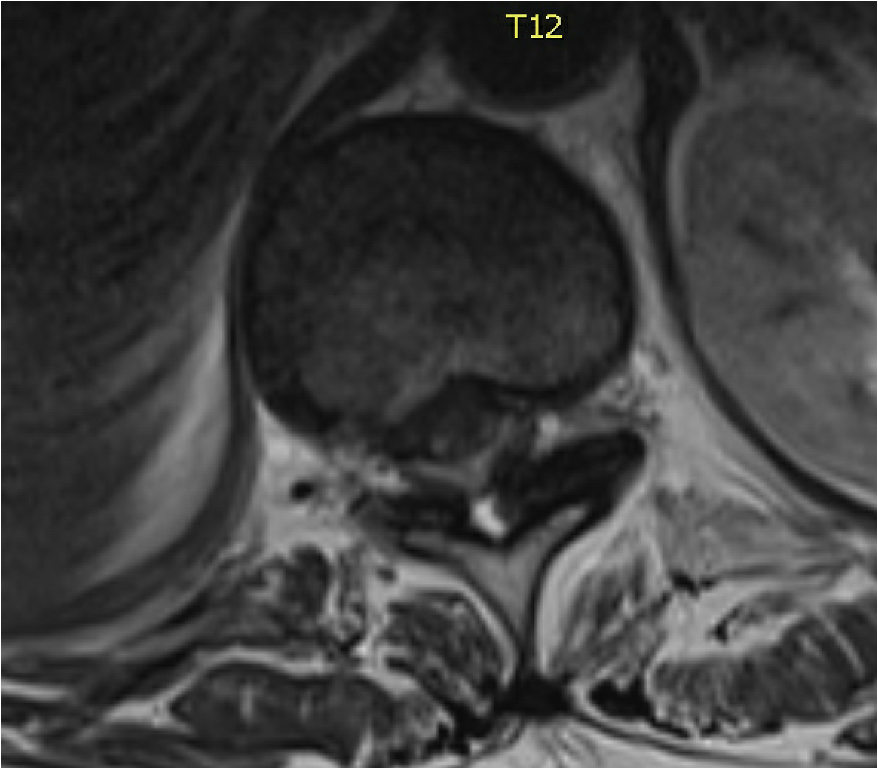

Congratulations to Dr. Michael Yang @MichaelYangMD and Dr. Ken Tomas who will be receiving 8.2 million dollars from the Calgary Health Foundation @yyc_health to build a Calgary Endoscopic Spine Surgery Program and an Enhanced Recovery After Surgery Program for Spine Surgery! 🙌